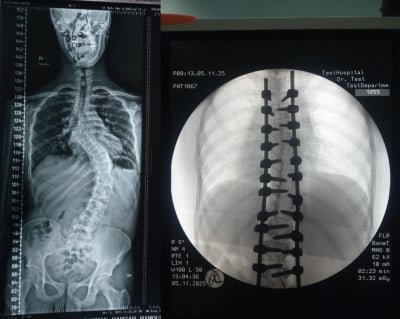

شهد قسم جراحة العمود الفقري في مستشفى الأمير حمزة إنجازًا طبيًا مميزًا تمثّل في إجراء تدخّل جراحي معقّد لتصحيح جنف العمود الفقري لدى أحد المرضى الذين يعانون من تشوّه حاد في الفقرات.

وقد أُجريت العملية باستخدام جهاز الملاحة الجراحية المتقدّم، الذي أتاح دقةً عالية في التعامل مع التشوّهات البنيوية الشديدة، وسهّل توجيه الأدوات الجراحية ضمن المسار الآمن والمثالي.

كما اشتملت العملية على إزالة أجزاء محددة من الأطراف الخلفية للفقرات لتحقيق التصحيح المطلوب واستعادة التوازن والمحاذاة الطبيعية للعمود الفقري.